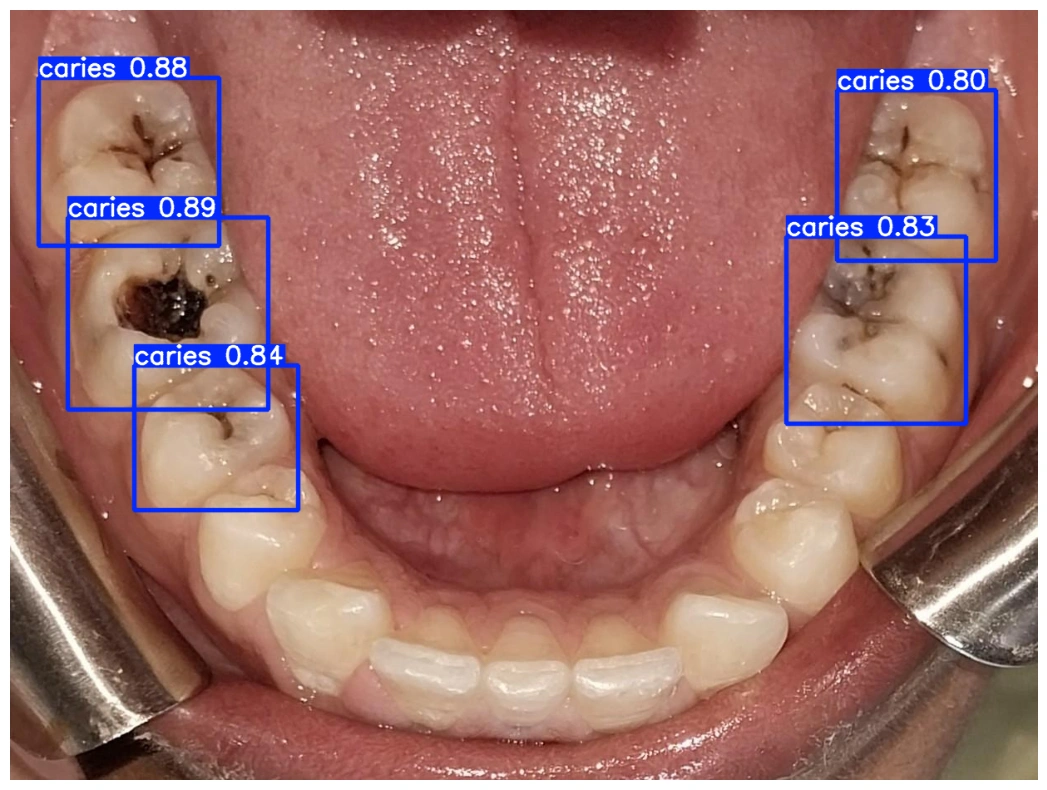

Пользователь открывает приложение, направляет камеру на полость рта, и нейросеть анализирует изображение, выделяя подозрительные зоны. Важно отметить, что технология не заменяет врача, а лишь дополняет диагностику. Например, система может указать на необходимость записи к стоматологу, но не ставит диагноз.

Проект основан на архитектуре YOLOv8, которая эффективно работает для анализа видеопотока с камеры. Версия YOLOv8n показала высокую точность и скорость обработки, что делает её подходящей для мобильных устройств. Выбор этой модели основан на сочетании практического опыта и научной базы в области стоматологической диагностики.

Для обучения модели использовался публичный датасет стоматологических снимков, предоставленный стоматологами из Пакистана, которые вручную отметили области кариозных поражений. Это позволило создать «золотой стандарт» для обучения нейросети. Первые результаты показали, что система может быть полезной: она обнаружила проблему у человека без жалоб, что подтвердил стоматолог.